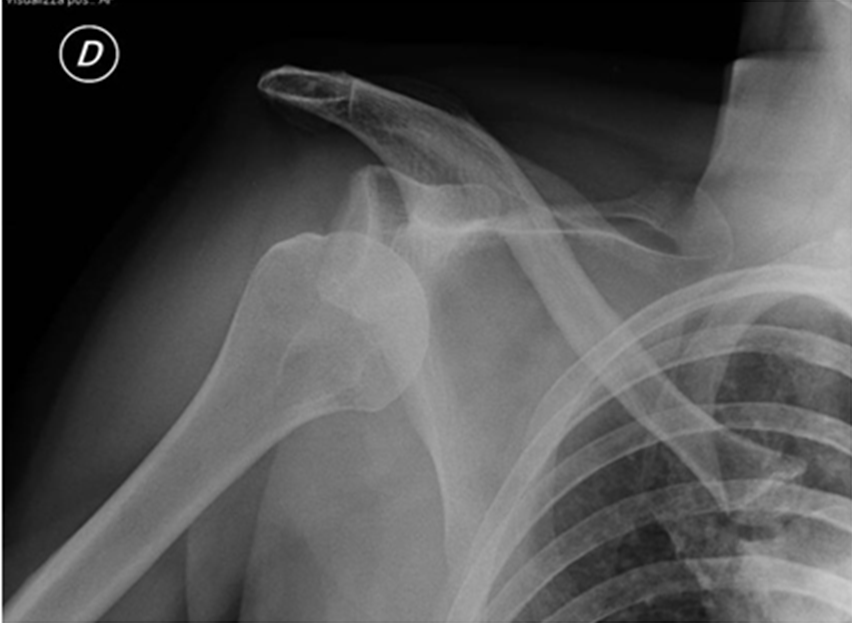

Radiographic analysis of antero-inferior glenohumeral luxation